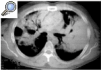

Fig. 2. Tomografía axial computarizada (corte axial): área extensa de condensación parenquimatosa con broncograma aéreo. Ausencia de adenopatías. Rodeadas del parénquima afectado existen áreas libres de enfermedad que conforman los quistes apreciados en la radiografía de tórax.